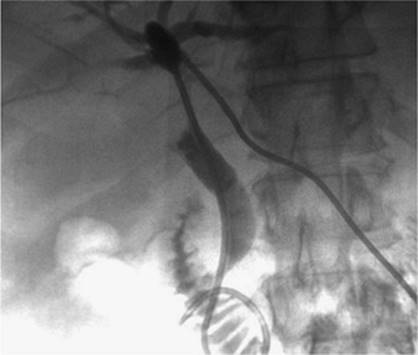

000443

Figure 35.17. On hospital day 2, internal/external drainage has been achieved by gaining access to the small intestine across the area of obstruction.

000250

Figure 35.18. This is the same patient as in Figures 35.16 and 35.17. A metallic self-expanding stent has been placed across the area of obstruction in the distal common bile duct. Note the waist in the stent (black arrow) due to the surrounding mass.

000446

Figure 35.19. Post–stent placement and balloon angioplasty. No residual stenosis is noted, and the stent is fully expanded.